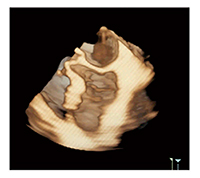

以前の超音波診断装置はmulti-beatでなければ時間・空間分解能を向上できなかったが,現在は技術の進歩により時間・空間分解能をほとんど損なうことなく1 beatでのフルボリューム撮像が可能となり,前述のASTRELLA CV-Linq上で解析可能となった。図3は,左室のFull Volume modeの画像であるが,このデータをASTRELLA CV-Linqの4D LV-Analysisに取り込み,僧帽弁,心尖部,大動脈弁の順に基準点を決定すると,3DスペックルトラッキングにてLV volume,stroke volume,ejection fraction(EF),global longitudinal strain(GLS),global circumferential strain(GCS)が表示される。臨床にてこれらの値が自動で得られることは大きなメリットであるが,この値の正確性や有用性については,今後検討する必要があると思われる。

図3 左室のFull Volume modeの

画像